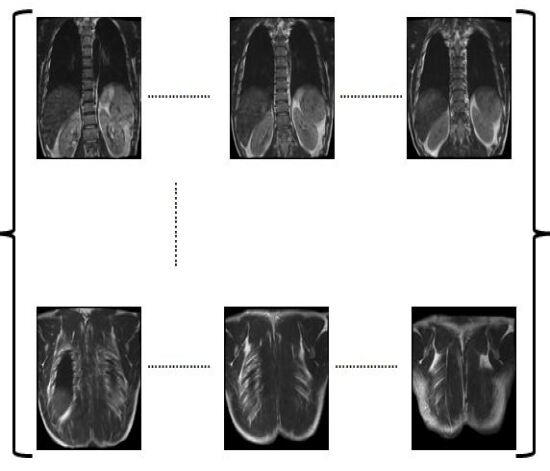

Figure 7: 3D Reconstruction of MRI for a human spine and slicing it along the three orthogonal planes as specified

In Figure 7 an example of 3D volumetric reconstruction, visualization as well as slicing are depicted. Figures 9, 11, 12 provide the results of our 3D reconstruction from a sequence of 2D slices for a full spine, a lumbar spine and a brain respectively. We compared the results after slicing with the available ground truth data (Figures 6, 8, 10, 13 for human lumbar along coronal, saggital, axial planes and human brain along sagittal plane respectively) based on mutual information, entropy, root mean square error and structural similarity index (see Appendix D). The average time taken by our 3D3𝐷3D reconstruction fo human spine is 54 seconds, depending on the size of the input data set. The time taken for slicing is a fraction of a second. The average accuracy percentage of our method, as shown in Table 2, is calculated as :